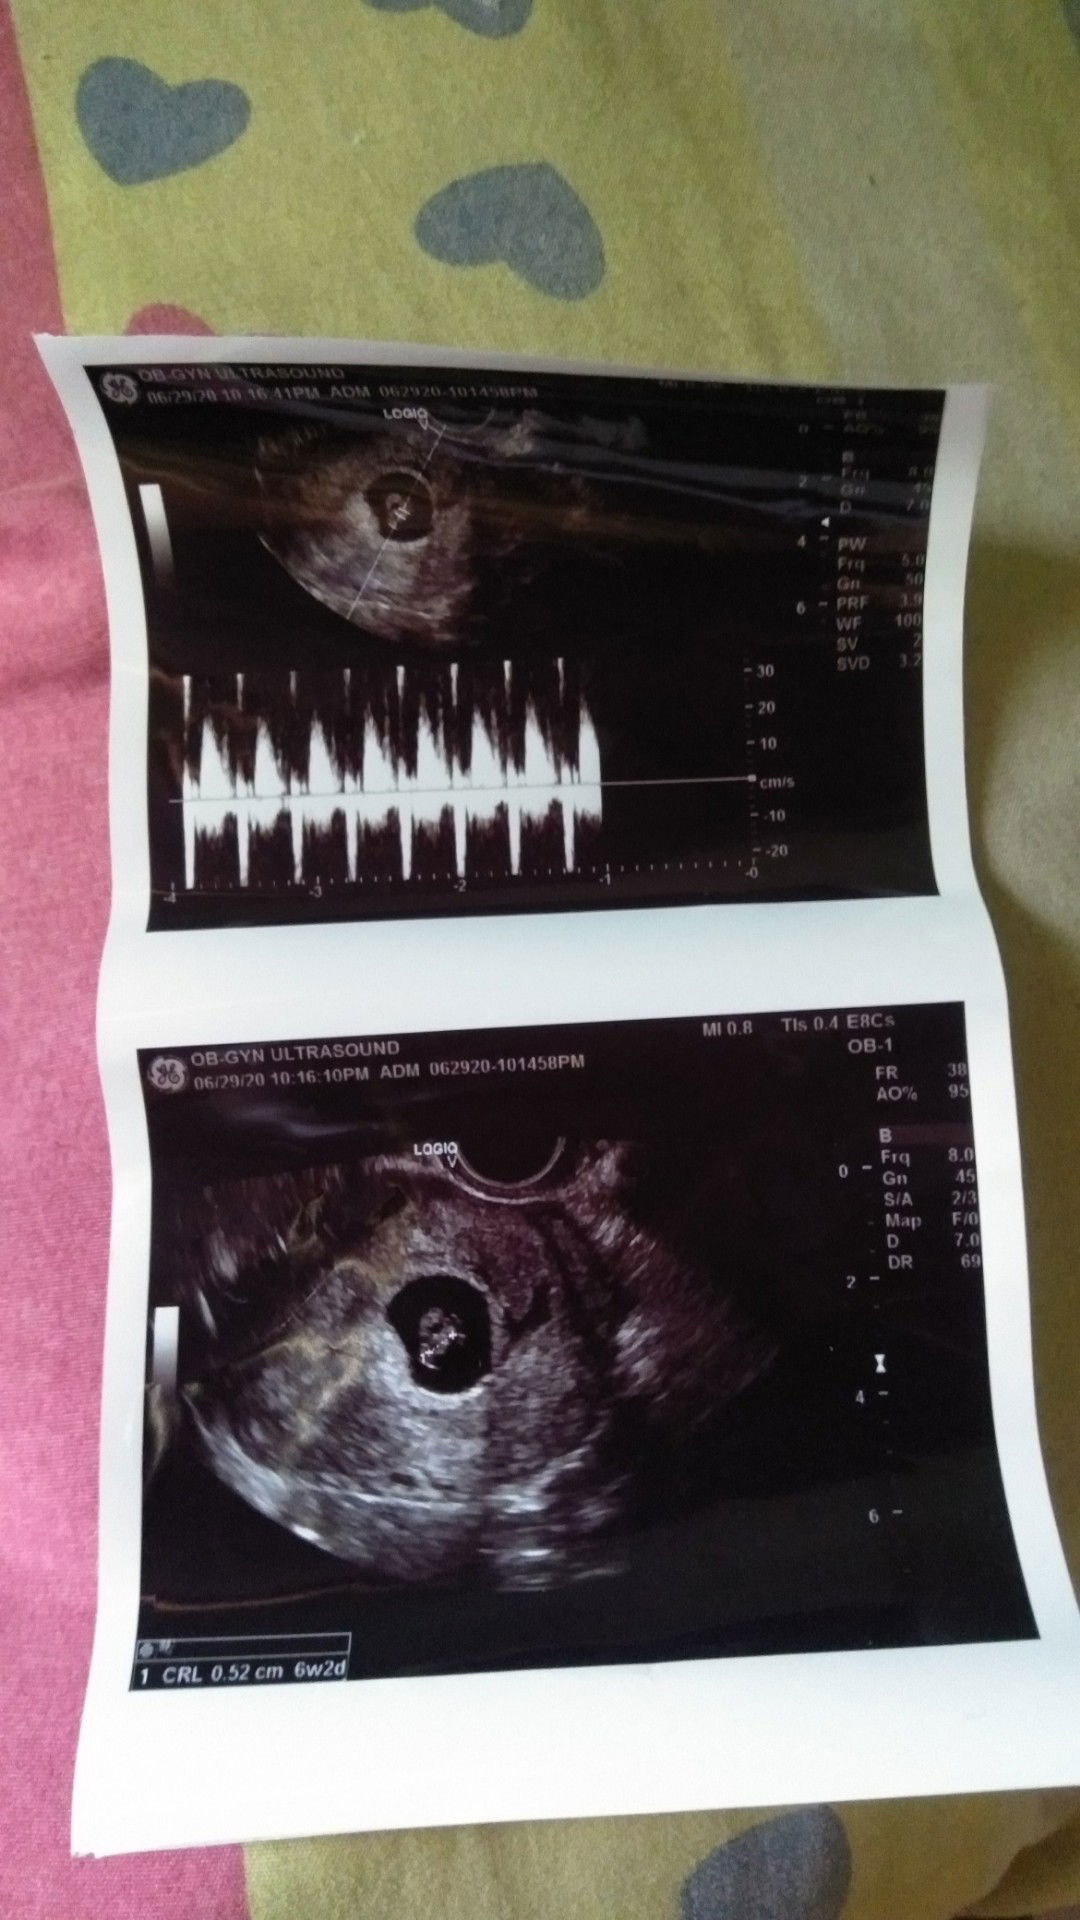

6weeks 2days

Finally! nakita ka na tagal kong nag antay Nakakatuwa kase narinig ko ang heartbet mo napakalakas 😍